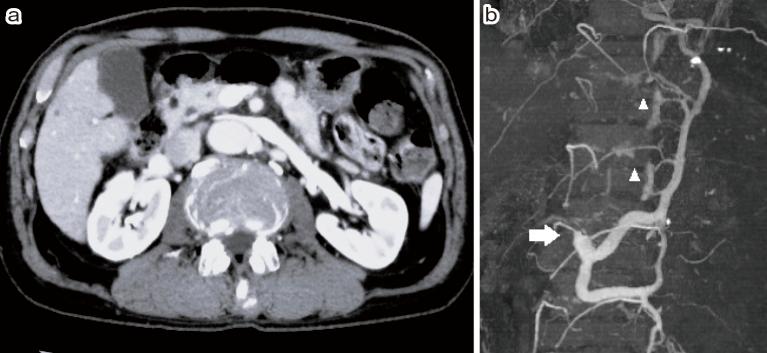

The causes of spinal epidural hematoma (SEH) have been attributed to coagulopathy, trauma, vascular anomalies, and so forth. The incidence of vascular anomalies shown by digital subtraction angiography has been reported to be 15%, and most cases have been reported to be spinal epidural arteriovenous fistulae. SEH has rarely been caused by venous congestion. We report a case of SEH in a 78-year-old male who presented to our emergency department with sudden-onset back pain, followed by complete paraplegia with bladder and rectal disturbance. Magnetic resonance imaging revealed a dorsally placed extradural hematoma extending from T10 to L1. An urgent laminectomy from T11 to L2 was performed. Computed tomography angiography (CTA) performed 1 week after the operation showed compression of the left renal vein between the aorta and superior mesenteric artery with dilation of the surrounding veins, including the spinal epidural venous plexus, at the same level as the hematoma. This was diagnosed as Nutcracker syndrome (NCS), which was consistent as a cause of SEH. The patient's symptoms gradually improved, and after 6 months, he regained normal strength in his lower extremities, but bladder and rectal disturbance remained and required intermittent self-catheterization. We chose conservative treatment for NCS, and SEH did not recur until the patient died of a cause unrelated to SEH or NCS. SEH could occur secondary to venous congestion including NCS. We emphasize the importance of investigating venous return to evaluate the etiology of SEH, which can be clearly visualized using CTA.

脊髓硬膜外血肿(SEH)的病因归因于凝血功能障碍、外伤、血管畸形等。数字减影血管造影显示的血管畸形发生率据报道为15%,且大多数病例据报道为脊髓硬膜外动静脉瘘。SEH很少由静脉淤血引起。我们报告一例78岁男性的SEH病例,该患者因突发背痛就诊于我院急诊科,随后出现完全性截瘫并伴有膀胱和直肠功能障碍。磁共振成像显示硬膜外血肿位于背部,从T10延伸至L1。紧急实施了T11至L2的椎板切除术。术后1周进行的计算机断层血管造影(CTA)显示,在与血肿同一水平,腹主动脉和肠系膜上动脉之间的左肾静脉受压,周围静脉包括脊髓硬膜外静脉丛扩张。这被诊断为胡桃夹综合征(NCS),与SEH的病因相符。患者症状逐渐改善,6个月后下肢恢复正常力量,但膀胱和直肠功能障碍仍然存在,需要间歇性自我导尿。我们对NCS选择了保守治疗,在患者死于与SEH或NCS无关的原因之前,SEH未复发。SEH可能继发于包括NCS在内的静脉淤血。我们强调调查静脉回流以评估SEH病因的重要性,使用CTA可以清晰地观察到静脉回流情况。